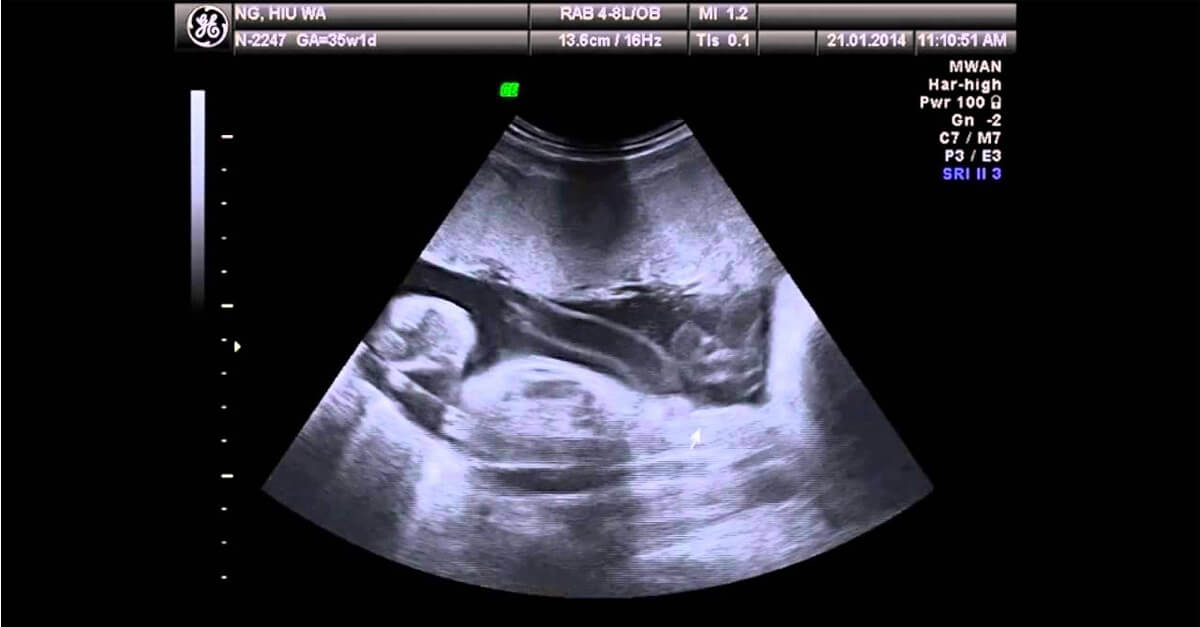

A avaliação do estágio da placenta é feita por ultrassonografia e, a partir disso, o médico vai definir os cuidados com a mãe e o bebê.